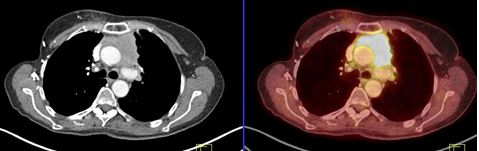

Los carcinomas tímicos (figs. 3, 4 y 5) se destacaron por un elevado metabolismo, con un SUVmax promedio de 10,4 (rango 5,6 a 13,2) y presentaron contornos irregulares, con compromiso de la grasa y de estructuras vecinas, presencia de calcificaciones, parálisis frénica (6 casos en 7) y siembra o derrame pleural o pericárdico (4 casos en 7).